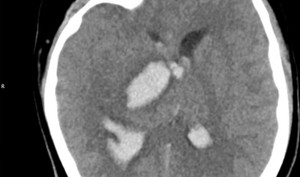

Chỉ với triệu chứng duy nhất là đau đầu, nam bệnh nhân 50 tuổi vẫn tỉnh táo, đi lại bình thường phát hiện tụ máu não kèm tràn máu não thất.